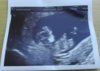

serduszko i cała reszta ok więc kamień z serca ale pewnie za kilka dni znów się stres zacznie i tak w kółko od wizyty do wizyty...